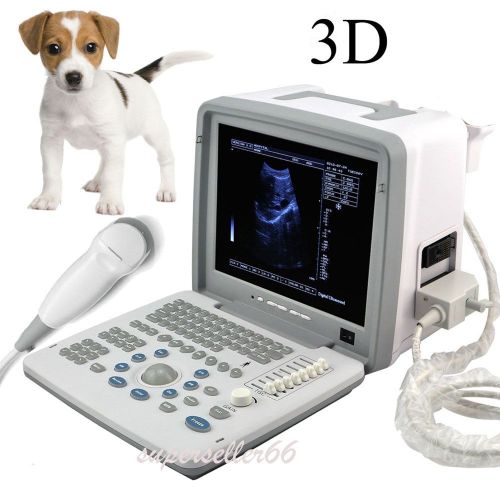

Model | 9000BV |

| Screen Size | 12 Inch | ||

| Machine Size | 31cm*21cm*27cm | ||

| Image resolution | 800*600 | ||

| Probe | Rectal probe | ||

| Options | Linear / Convex / Micro-Convex |

12-inch Veterinary Portable Digital Ultrasound Scanner Convex Probe External 3D